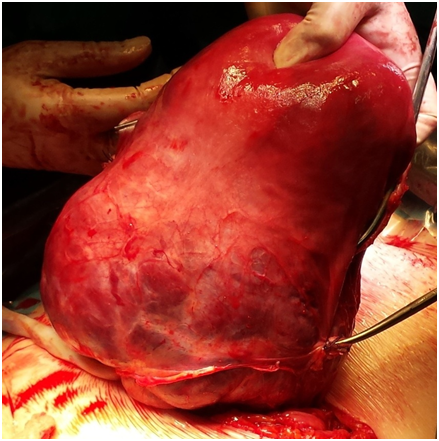

A 31-year-old woman (gravida VI, para III) with no concomitant diseases and a history of prior cesarean section due to placenta previa. During pregnancy was made regular 1st and 2nd trimester ultrasonography to rule out fetal pathology and a low-lying or adherent placenta, but the scan did not show any signs of an abnormal placenta or other problems. On admission 13.06.2016 at 3:15am, the patient presented frequent voiding of urine and pulling abdominal and spinal pain. A day before hospitalization was referred to hospital due to abnormal placentation diagnosed during a routine sonographic examination at 35/36 weeks of gestation. An urgent abdominal ultrasound examination in hospital showed a viable fetus with appropriate biometrical parameters and normal amniotic fluid, while Eco-Doppler images suggested the diagnosis of placenta increta suspecta. Careful evaluation of the placenta with pelvic noncontrast magnetic resonance imaging confirmed the ultrasound diagnosis. The patient was made aware of the potential obstetric complications. An elective cesarean delivery was planned at 36+2 weeks of gestation. Because she had received spinal anesthesia for her previous cesarean sections, this surgery was also planned with spinal anesthesia. The caesarean surgery was performed as usual. 17.06.2016 at 9:05am a healthy female baby, with weight 2,540 g was delivered. In connection with the diagnosis was made hysterectomy, the resulting material was sent to histological examination. The operation lasted 45 minutes and the patient lost a lot of blood. After all the seams are laid in the pelvic floor was left drain and the abdomen was closed using a regular technique. During the surgery, the patient lost 2000 ml of blood and developed severe hemodynamic instability, with a 10% – 20% decrease in systolic blood pressure. A transfusion protocol was initiated. Intraoperative allogeneic red blood cells (556 ml) and free-frozen plasma (988 ml) were transfused. The patient was cared for in the intensive care for one day. The postoperative course was uneventful, and the patient was discharged on day 7 in good conditions.6-8

Figure 3 Operation stage, uterus after C-section and before extirpation.